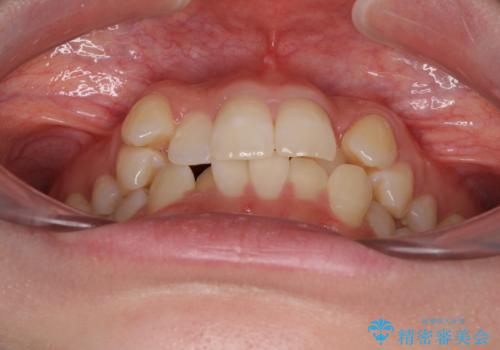

- 八重歯が気になるとのことで来院された患者様です。

上顎前歯部はデコボコが強く、歯を並べるためのスペースが不足しているため、左右の第一小臼歯を抜歯することとしました。

矯正治療の前に上下左右の親知らずの抜歯も行いました。